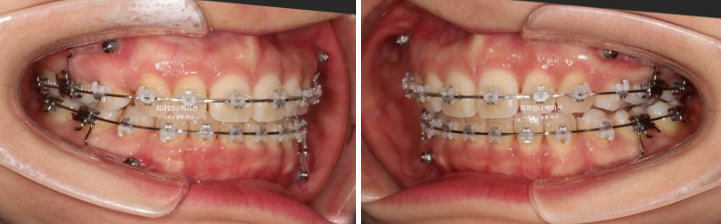

치료시작 1년차인 2023년 9월 발치공간이 절반가량 남은 상황에서 앞니를 더 이상 뒤로 넣지 않는 것이 좋겠다고 판단되었습니다.

그래서 옆얼굴 엑스레이와 사진촬영 자료를 통해 환자분과 상의하고 향후 남은 공간은 어금니를 앞으로 당겨와 발치공간을 마무리 하기로 합니다.

앞니가 더이상 뒤로 들어가지 않도록 유지하며 발치공간을 마무리 하는 것으로 치료계획이 변경 되었습니다.

큰어금니를 발치공간으로 끌어오는 방법은 교정용 나사를 앞쪽에 4개를 심고 어금니를 앞으로 끌어주는 고무줄을 겁니다. 큰어금니가 쓰러지지 않고 뿌리까지 잘 당겨져 오려면 힘의 작용점등 생역학적인 고려가 필수입니다.

24.06